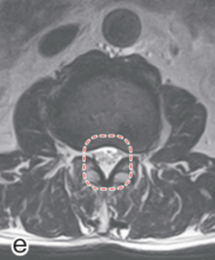

画像所見

レントゲン像 MRI像